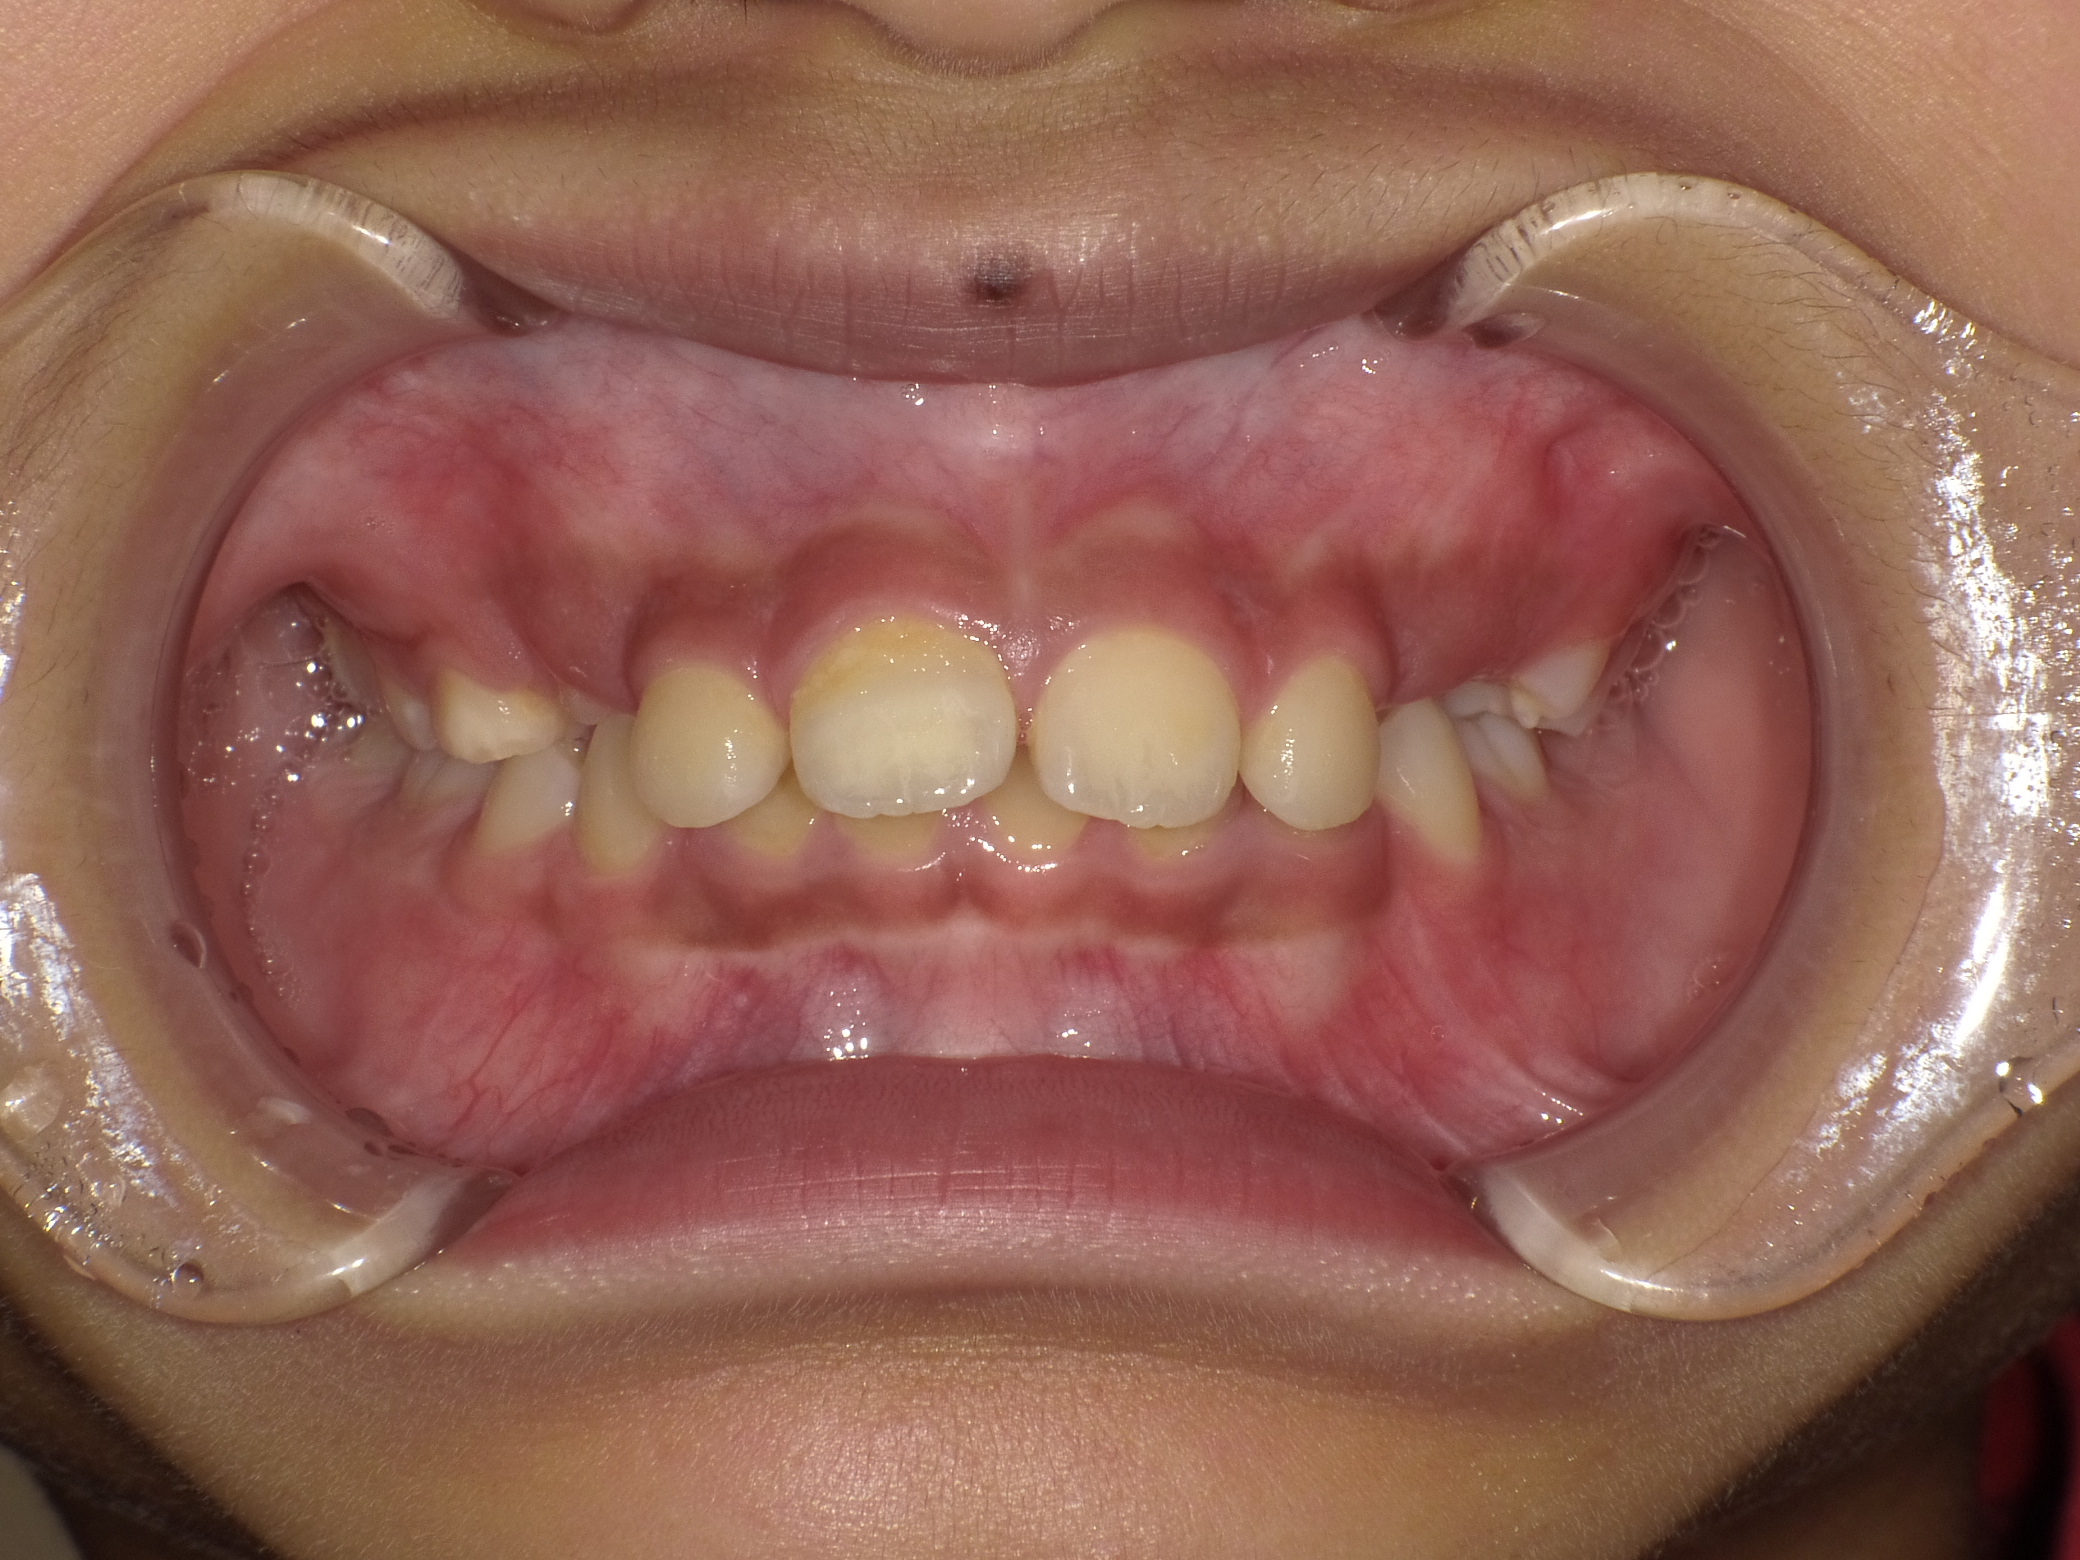

上下顎前突 10歳8ヶ月 男の子

10歳8ヶ月 男子

治療前

お悩み:

口元の突出感(前歯が出ている)と見た目の改善

状態:

骨格:上下あごともに前方に出やすい傾向(上下顎前突)

歯並び:前歯の前方への突出(出っ歯傾向)